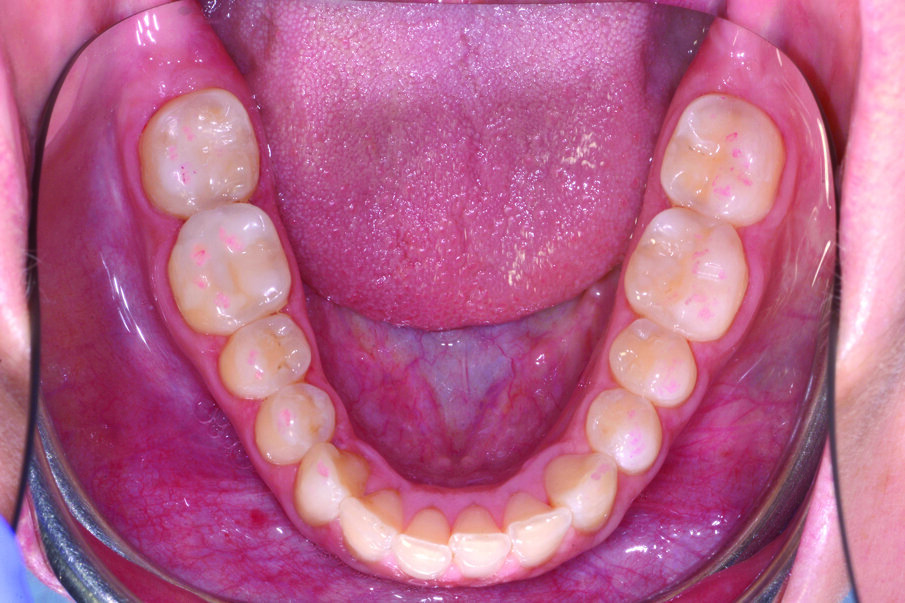

Nel seguente caso clinico, viene eseguita una riabilitazione ultraconservativa da canino a secondo molare su un giovane paziente che denuncia una perdita di dimensione verticale a causa di erosioni e abrasioni che interessano tutti gli elementi del mascellare inferiore da canino a secondo molare.

Fig. 1a_Caso iniziale: il paziente presenta perdita di dimensione verticale a causa di erosioni e abrasioni.